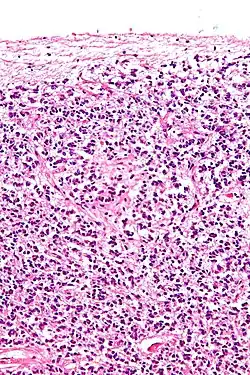

Cross-section of pineal gland displaying pinealocytes and other cells | |

Pinealocytes are the main cells contained in the pineal gland, located behind the third ventricle and between the two hemispheres of the brain. The primary function of the pinealocytes is the secretion of the hormone melatonin, important in the regulation of circadian rhythms.[1] In humans, the suprachiasmatic nucleus of the hypothalamus communicates the message of darkness to the pinealocytes, and as a result, controls the day and night cycle.[2] It has been suggested that pinealocytes are derived from photoreceptor cells.[3][4] Research has also shown the decline in the number of pinealocytes by way of apoptosis as the age of the organism increases.[5] There are two different types of pinealocytes, type I and type II, which have been classified based on certain properties including shape, presence or absence of infolding of the nuclear envelope, and composition of the cytoplasm.

Type 1 pinealocytes are also known as light pinealocytes because they stain at a low density when viewed under a light microscope and appear lighter to the human eye. These Type 1 cells have been identified through research to have a round or oval shape and a diameter ranging from 7–11 micrometers.[6] Type 1 pinealocytes are typically more numerous in both children and adults than Type 2 pinealocytes.[6] They are also considered to be the more active cell because of the presence of certain cellular contents, including a high concentration of mitochondria.[7] Another finding consistent with Type 1 pinealocytes is the increase in the amount of lysosomes and dense granules present in the cells as the age of the organism increases, possibly indicating the importance of autophagocytosis in these cells.[6] Research has also shown that Type 1 pinealocytes contain the neurotransmitter serotonin, which later is converted to melatonin, the main hormone secreted by the pineal gland.[8]

Type 2 pinealocytes